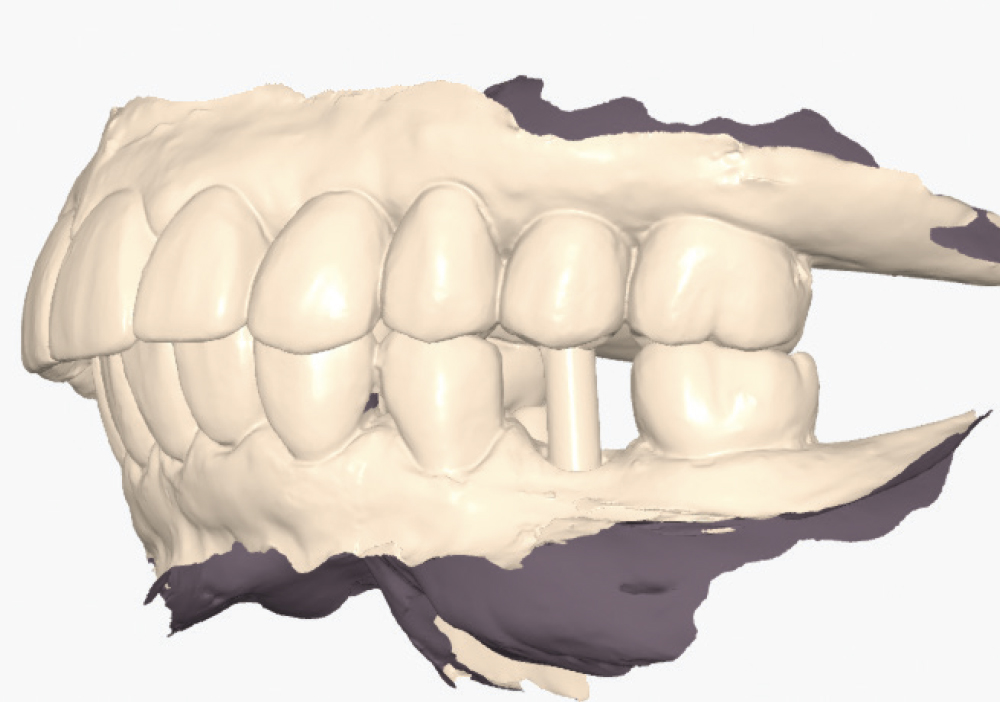

Implant post scan on left side of mouth

Implant post scan pointing down

Implant post scan close up

Verify the Scans Before Dismissing the Patient. Review all critical areas while the patient is still in the chair, ensuring complete scan body capture, accurate contacts, adequate tissue detail, and proper bite registration. Zoom in on critical areas to verify resolution and completeness. It takes only two minutes to verify a scan, but potentially days before a patient is able to return to your practice. Use the scanner’s analysis tools to identify distortions or artifacts.